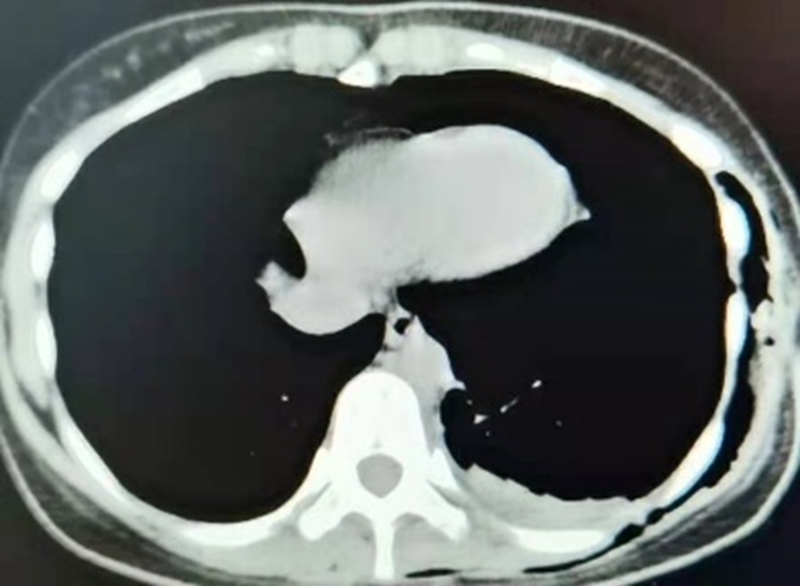

术后

经检查后发现,该患者肿瘤位于后纵隔脊柱旁,大小约5cm×4cm×3cm,与胸主动脉、食管及脊柱关系密切。为了给这位年轻的患者制定更加科学、优质、个性化的治疗方案,科室立即组织专家进行讨论,考虑后纵隔肿瘤可行胸腔镜手术切除,且术后可免行胸腔闭式引流术;6月18号行经单孔胸腔镜下行纵隔肿瘤切除术,术中无出血,术后胸腔免留置胸腔引流管,术后当天患者即下床活动,仅有切口轻微疼痛;术后第2天切口无明显疼痛,康复出院。